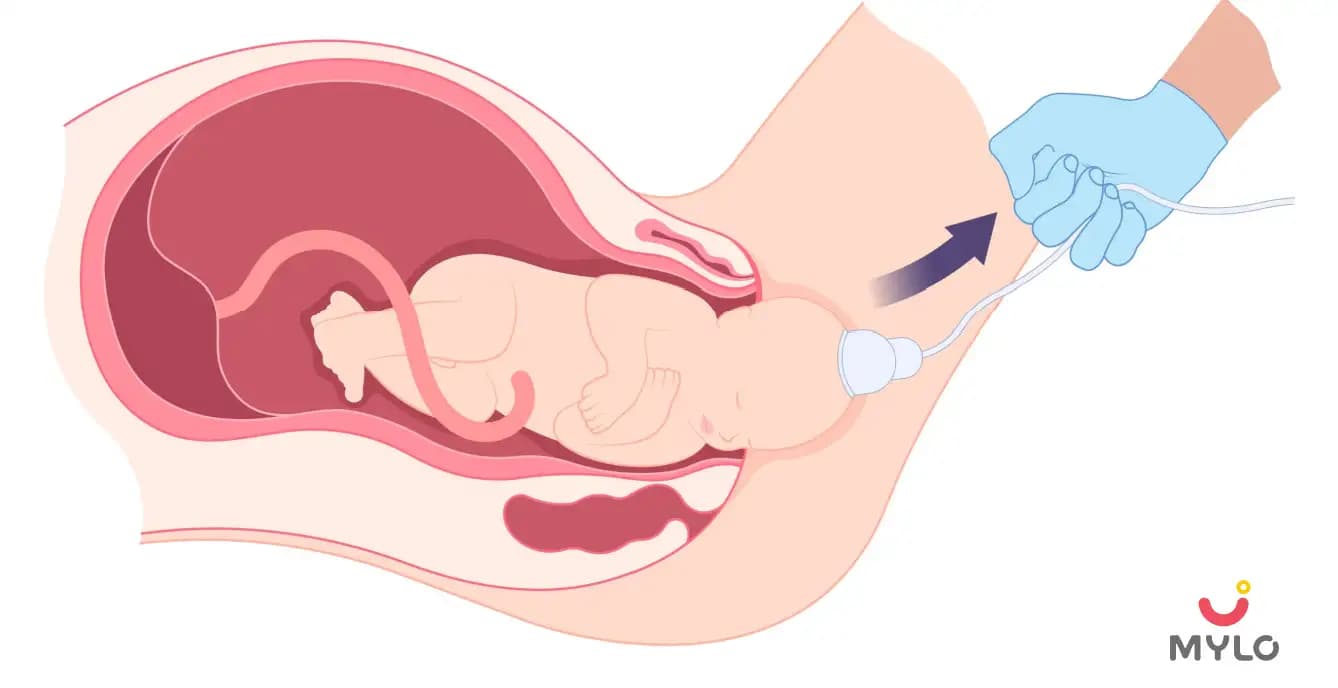

Things Pregnant Women Should Know About Vacuum Delivery